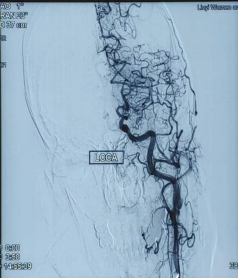

有一名老年女性患者,3月前出现头晕、言语不清,自觉舌头僵硬,就诊于我院内科门诊行颅脑磁共振平扫:新发脑梗死;颅脑血管磁共振:双侧大脑中动脉未见明确显示,颅内较多侧支血管形成,考虑烟雾病,建议脑血管造影检查。住院期间行脑血管造影:

看到这些图,瞬间让人想起了天青色等烟雨,而我在等你,炊烟袅袅升起......

烟雾病(Moyamoya disease,MMD),又称颅底异常血管网病,是颈内动脉虹吸部及大脑前动脉、大脑中动脉起始部严重狭窄或闭塞,软脑膜动脉、穿通动脉等小血管代偿增生形成脑底异常血管网为特征的一种脑血管疾病。其脑血管造影可见脑底密集成堆的小血管,酷似烟雾,故称为“烟雾病”。